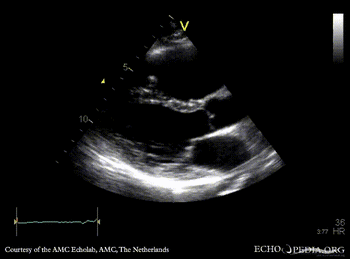

Case 48